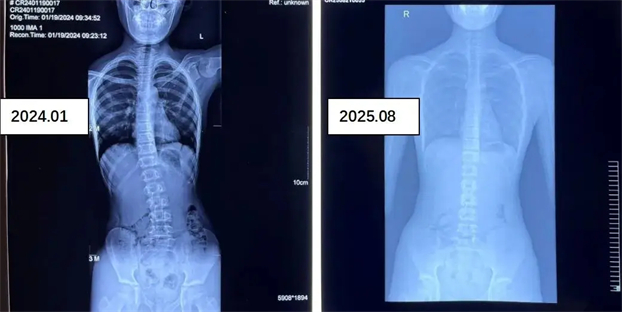

参加康复医学科脊柱侧弯训练营青少年前后对比照

康复医学科主任医师领衔,团队包含主治医师、主管治疗师、康复治疗硕士等专业人才。多次开展夏季、冬季训练营,常年开展周末训练营,成功帮助诸多青少年改善体态、恢复脊柱正常序列。

影像学评估:全脊柱 X 光片测量 Cobb 角,明确侧弯程度